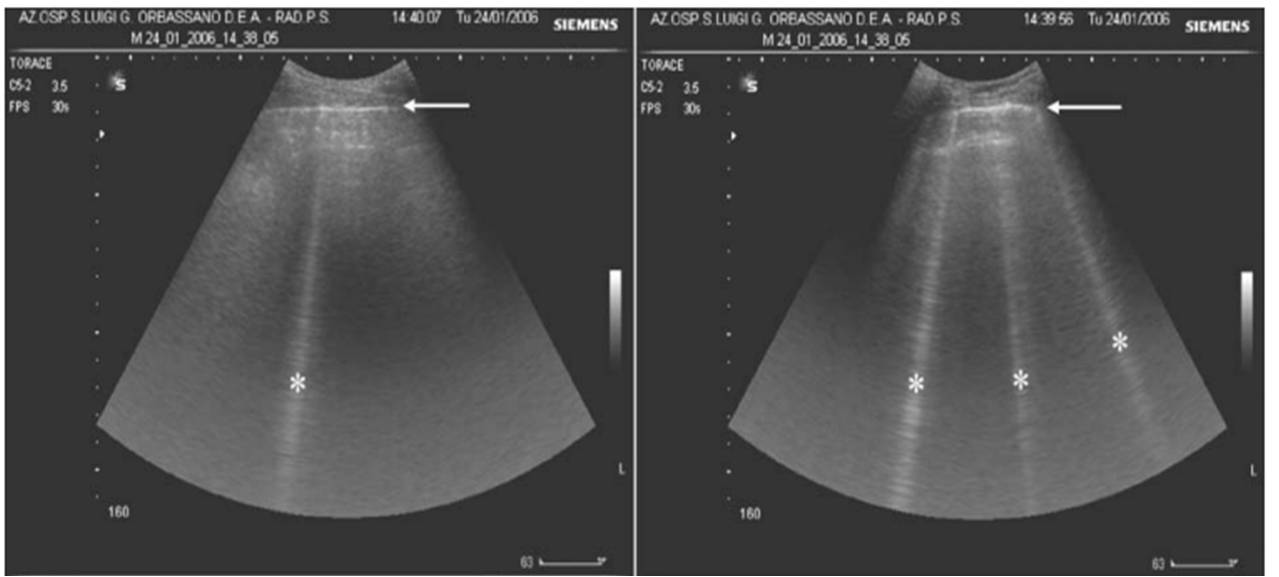

Figure 031_1172. Multiple B lines (arrows) with confluent B lines

Figure 031_1172. Multiple B lines (arrows) with confluent B lines B Line Meaning Origin When a forager bee finds a source of. The word originated in the us almost 200 years ago. According to the oxford english dictionary, one of the first. A beeline is the shortest distance between two points, as in to ‘make a beeline’ for or to a place. It is american in origin and dates. (occasionally) the course taken by. B Line Meaning Origin.